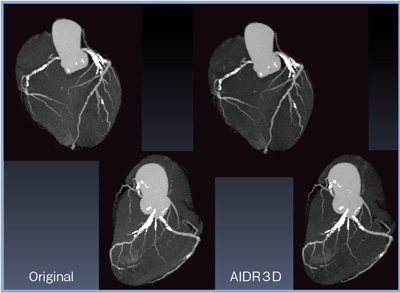

オリジナル画像と,AIDR 3Dによる再構成画像を比較すると,AIDR 3Dによってノイズが低減していることが確認できる。

MIP画像ではノイズの低減が確認できるとともに,RCAの末梢や細い血管領域が明瞭に描出されていることが確認できる(図4)。

図4 AIDR 3Dの有無による比較(MIP画像)